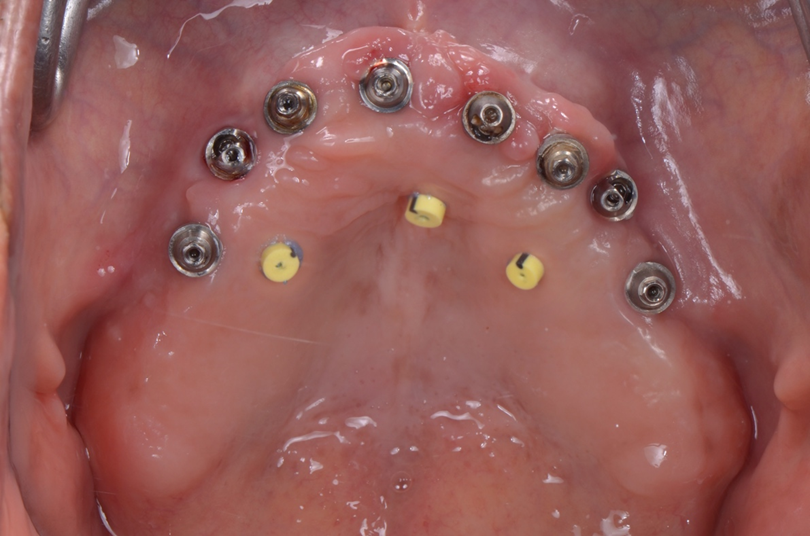

Foi realizado uma técnica baseada no Double Digital Scanning (DDS)2 seguindo o fluxo Full Arch Implant do software Dexis IS ScanFlow v1.0.10. Um primeiro escaneamento (arquivo 1), chamado de Digitalização normal (vide Figura 1), com a prótese fixa em posição, é realizado após a colocação dos três cursores colados na mucosa do palato duro com Top Dam, para servirem como pontos de referência (Figura 3). Em seguida, foi realizado o escaneamento do antagonista e a oclusão. Depois, os dados desse primeiro escaneamento são copiados para a Digitalização de referência (vide Figura 1). Posteriormente, a prótese fixa foi removida e um escaneamento (arquivo 2), chamado de Digitalização do corpo de digitalização (vide Figura 1), foi feito após os transferentes digitais dos Mini Cônicos (Implacil De Bortoli, São Paulo – SP) terem sido apertados manualmente com os mesmos cursores colados para servirem como pontos de referência no lugar também (Figura 4). Os arquivos digitais gerados a partir dos dois escaneamentos intraorais (arquivos 1 e 2) da prótese fixa em posição (com o antagonista e a oclusão) e dos transferentes dos Mini Cônicos foram salvos.